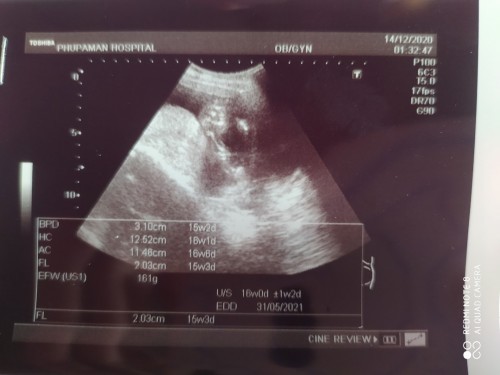

พึ่งไปซาวด์มาเมื่อวานคุณหมอก็บอกว่าน้องตัวเล็กมากๆ(แอบกังวนอยู่ค่ะเพราะแม่แพ้ท้องหนักมากไม่รู้จะบำรุงไงดี) หมอก็ไม่มั่นใจเรื่องเพศ แต่บอกน่าจะได้เพศชาย อยากให้แม่ๆท่านอื่นช่วยดูด้วยค่ะว่าเพศอะไรกันแน่ #ขอคำแนะนำหน่อยค่ะ #ท้องแรกคะ #ขอบคุณสำหรับคำตอบค่ะ #ขอบคุณล่วงหน้านะคะ